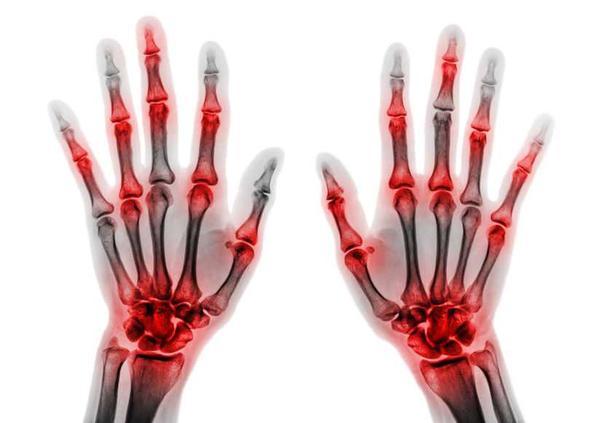

痛风石是痛风诱发的并发症之一,当其出现后,最典型的症状就是关节红肿,疼痛,如果没有及时治疗,久而久之,关节破骨细胞以及骨头等部位便容易受到损伤;

同时影响软骨细胞和软骨的生存能力,严重的话甚至还会破坏肌腱,给关节造成不可逆的损伤。

痛风石之所以恐怖,原因在于病情不断发展的过程中容易逐渐的侵蚀骨骼,导致关节急性炎症发生,这样一来患者不光会有骨头疼痛的感觉,同时还会影响正常的活动。

特别是痛风时发展速度较快的情况下,还有可能降低关节功能,出现畸形问题。